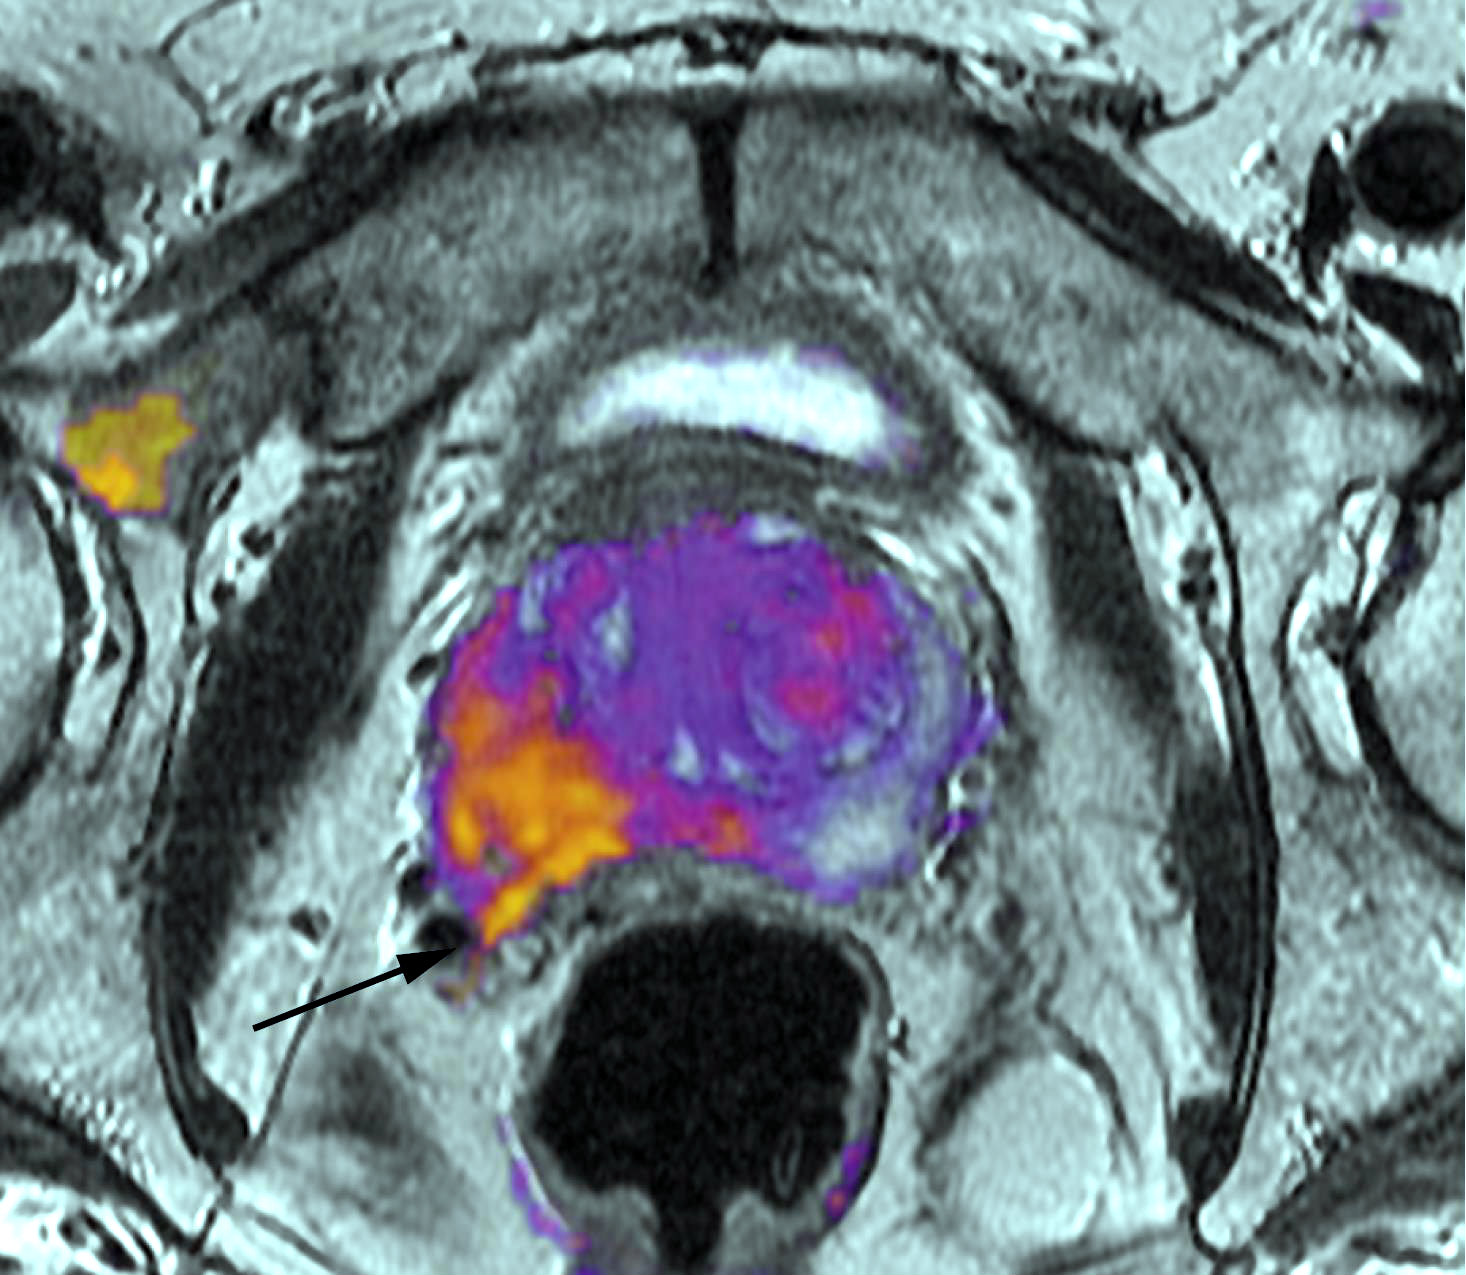

Un ensayo clínico muestra aumento en la sobrevida del cáncer metastásico sumando quimioterapia a la terapia de deprivación androgénica. En otro estudio, la mitoxantrona no fue eficaz luego de la prostatectomía de tumores de altor riesgo sin metástasis. Journal of Clinical Oncology, abril de 2018